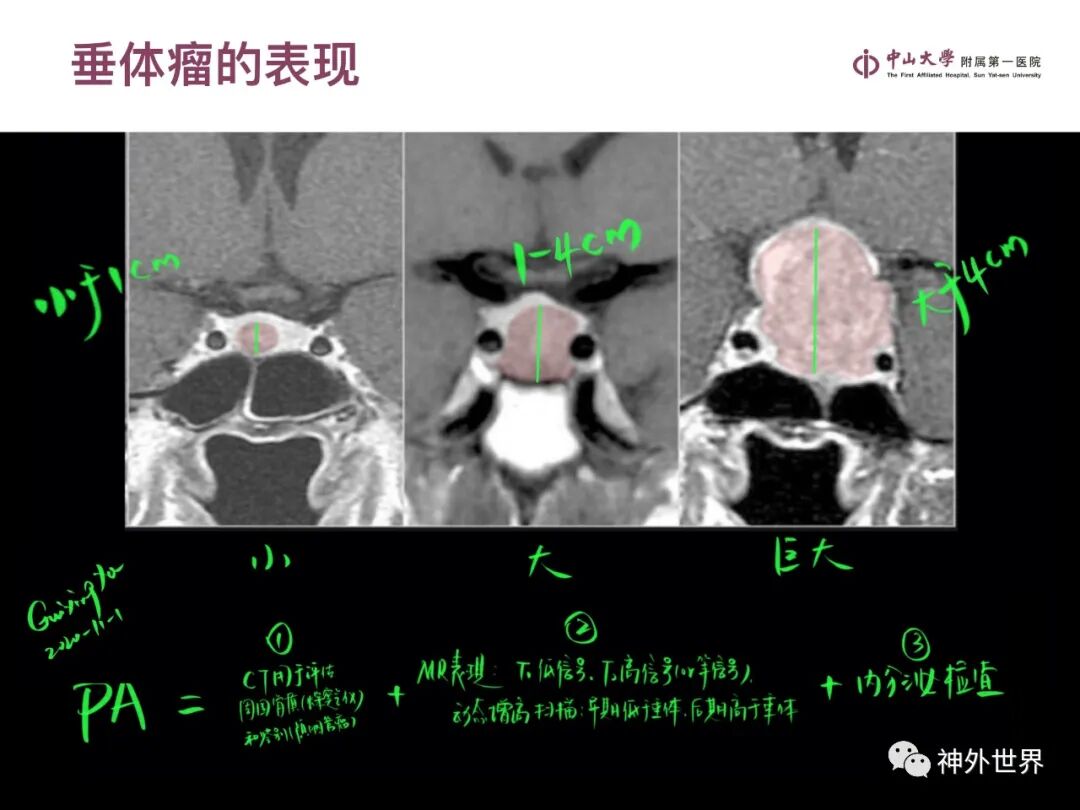

大脑MR、CT 的阅片技巧,超赞 !